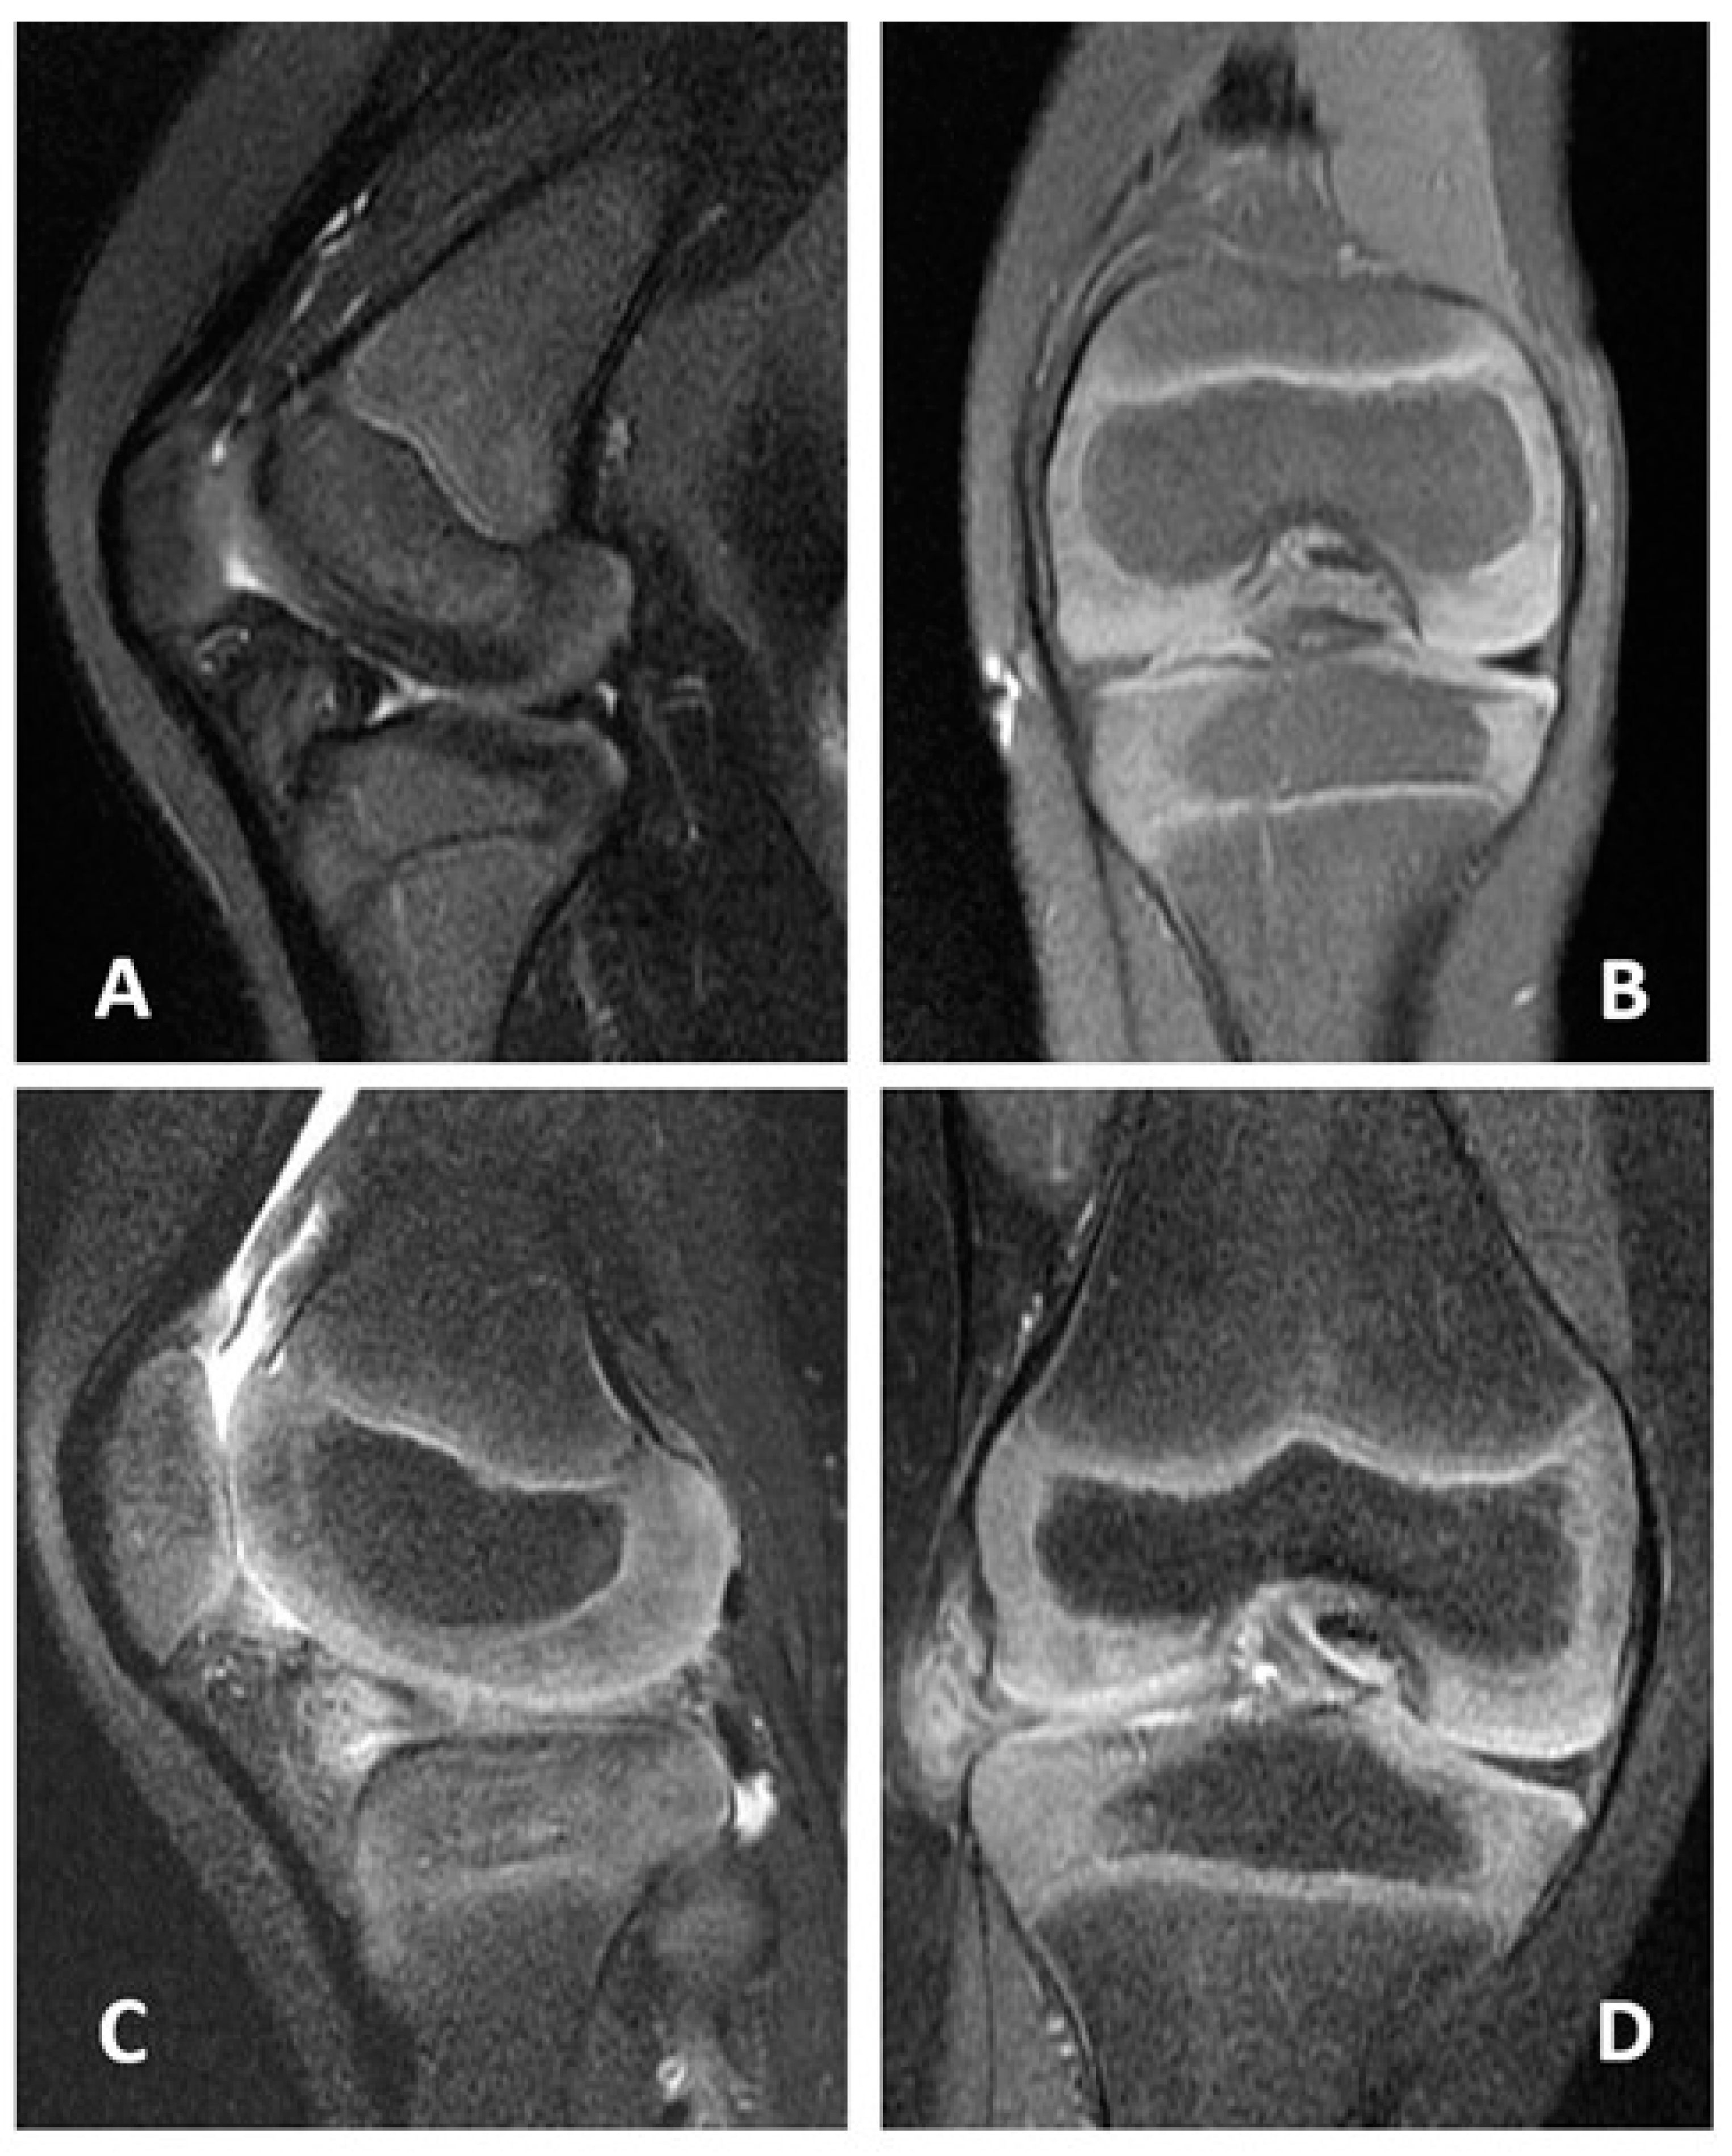

2.1. Case 1

2.2. Case 2